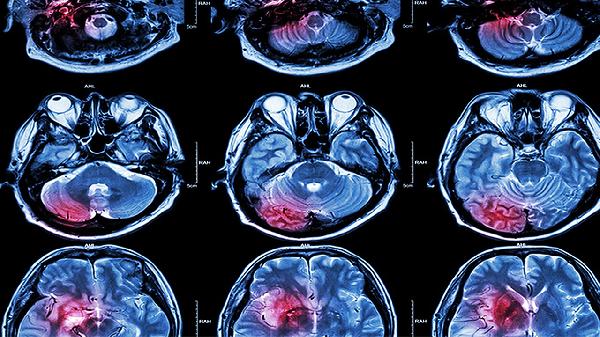

血管瘤是一种常见的良性肿瘤,通常不会引起生命危险。大多数血管瘤是先天性的,但也可能在后天生长过程中形成。血管瘤通常分为两种类型,毛细血管瘤和海绵状血管瘤。前者是由毛细血管聚集而成的,多表现为红色或紫色的皮损,通常在出生后出现,在第一年内会自行消退或变得更小。后者则是由血管窦或海绵状丛集而成的,表现为软组织肿块,可能会在生长过程中破裂出血。对于血管瘤8x7mm,如果位于部位较为敏感或存在明显临床症状,如出血、压迫神经等,则需要进行进一步的检查和治疗。通常采用超声、CT检查、磁共振检查等检查方法评估病变的大小、部位、病情轻重等情况,以确定最适宜的治疗方案。治疗方法可能包括手术切除、激光治疗、放射线治疗等。